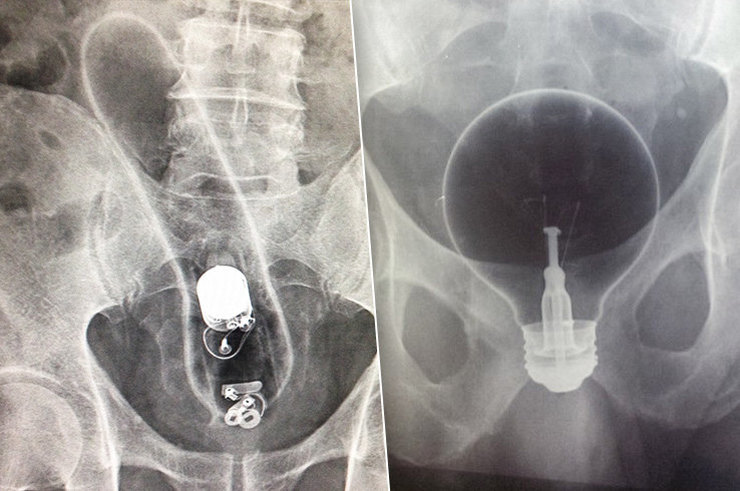

Врачи неоднократно сталкивались с разными видами секс-игрушек, случайным образом затерявшихся в недрах людей, которые слишком сильно увлеклись мастурбацией. Но такое они видели впервые: во влагалище 38-летней шотландки был обнаружен дилдо, пропавший десять лет назад.

Пациентка жаловалась на потерю веса, кататонию, тремор и обмороки. Медицинский состав Абердинской королевской клиники убедил женщину рассказать о своей интимной жизни, и выяснилось, что 10 лет назад ее партнер уговорил ее воспользоваться секс-девайсом. Оба партнера были сильно пьяны, так что, вероятно, просто не заметили пропажи…

У женщины был диагностирован пузырно-влагалищный свищ, то есть между ее мочеполовым трактом и влагалищем было обнаружено отверстие. Из-за застрявшей игрушки моча собиралась в почках и вызывала эти симптомы.